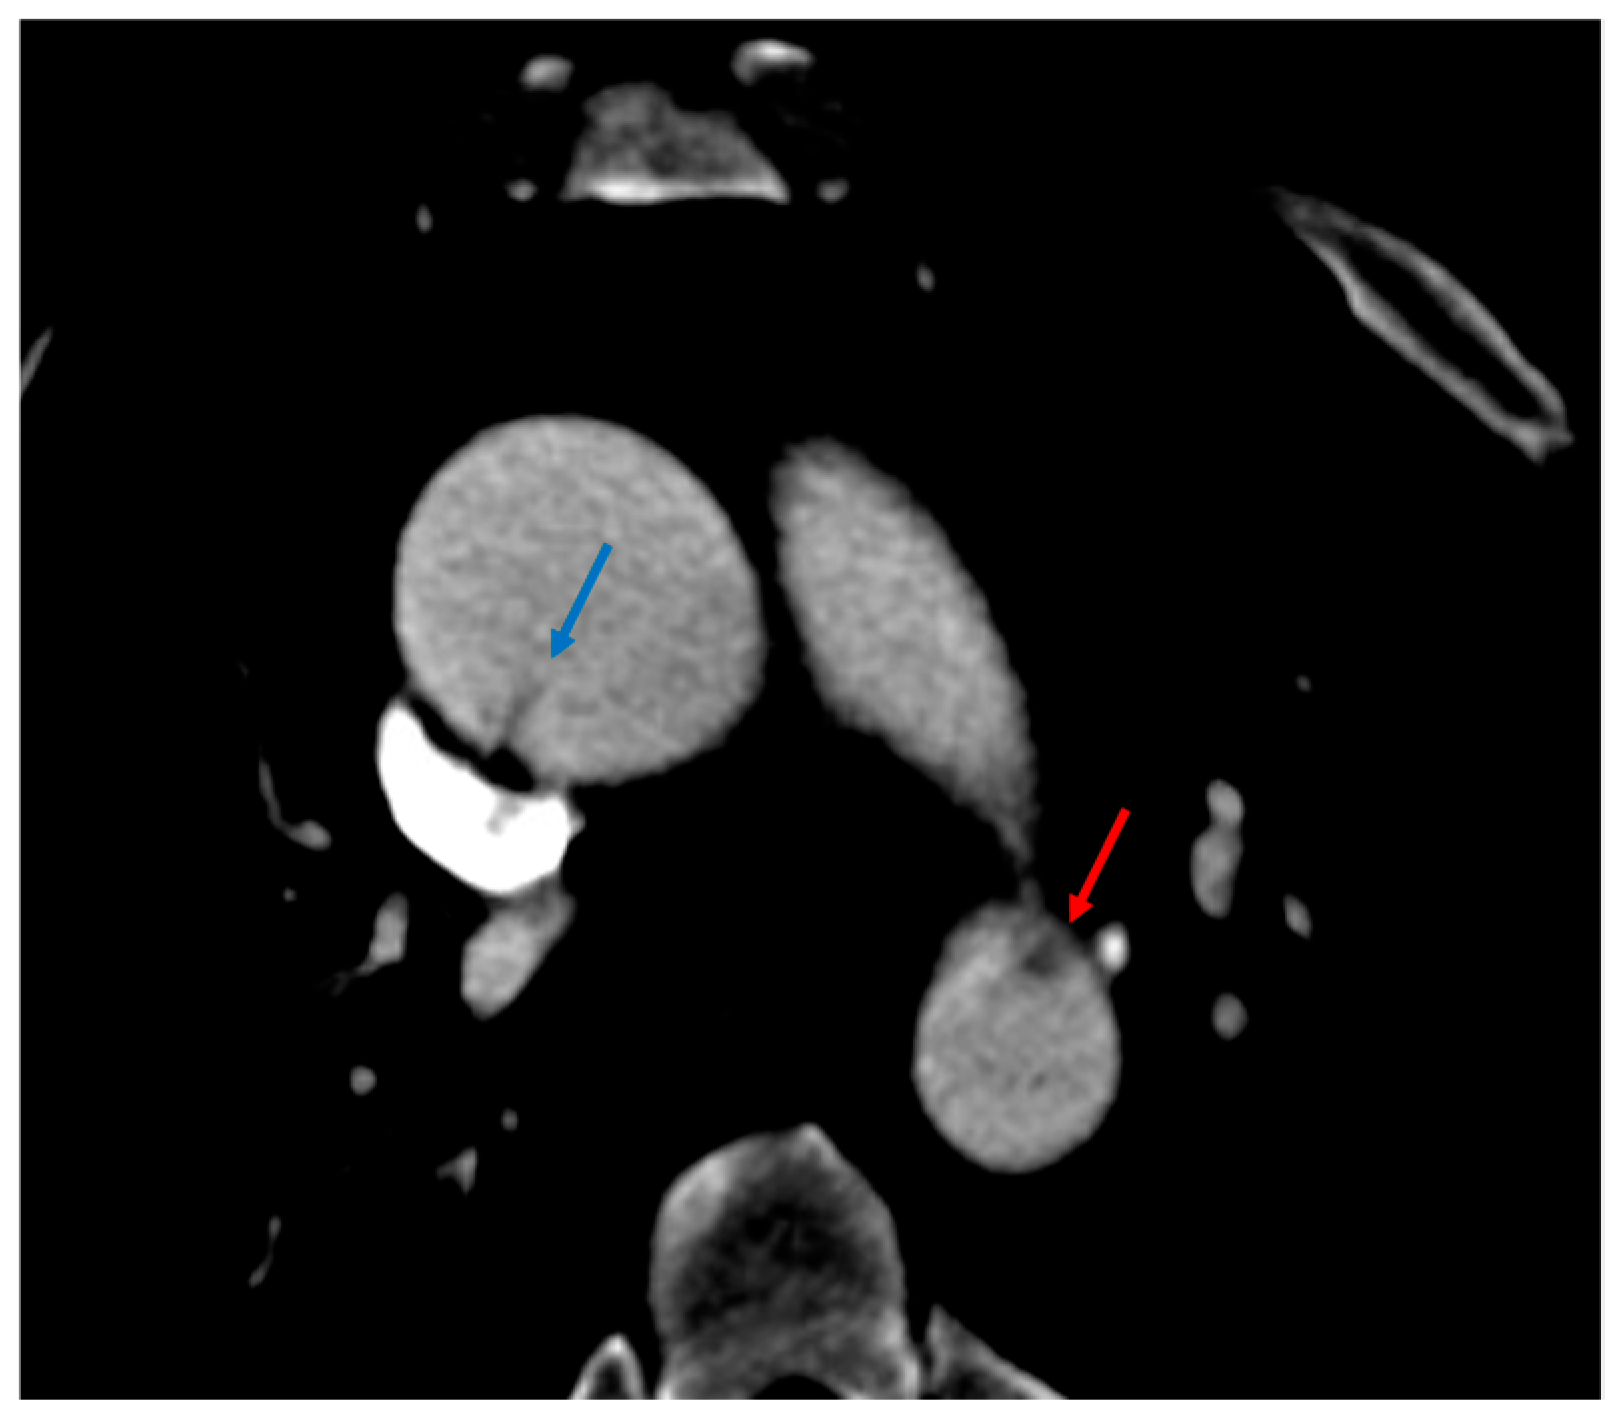

3.1.5. CT Angiography Artifacts

3.1.6. ECG-Gated CT Angiography